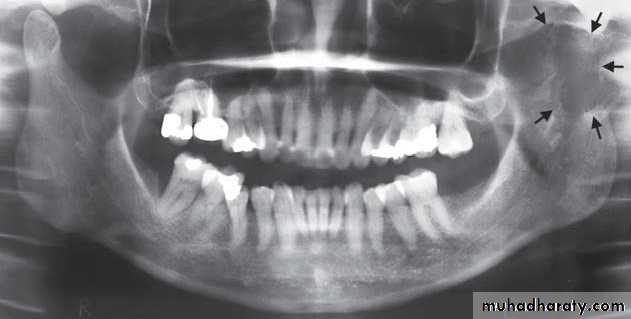

3- Coronoid Hyperplasia:

- Acquired or developmental- Elongation of the coronoid process

- Developmental > bilateral.

Acquired > uni or bilateral.

-Inability to open mouth.

-Painless.

Radiographic features:

• TMJs usually appear normal

• Unilateral cases should be

differentiated from a tumor of the

coronoid process (osteochondroma or osteoma)

• Unlike coronoid hyperplasia, tumors have an irregular shape

• Treatment: surgical removal or the coronoid process and postoperative physiotherapy

Sagittal CT. Elongated coronoid process extends above the inferior rim of the zygomatic arch (arrow)

with normal shaped .